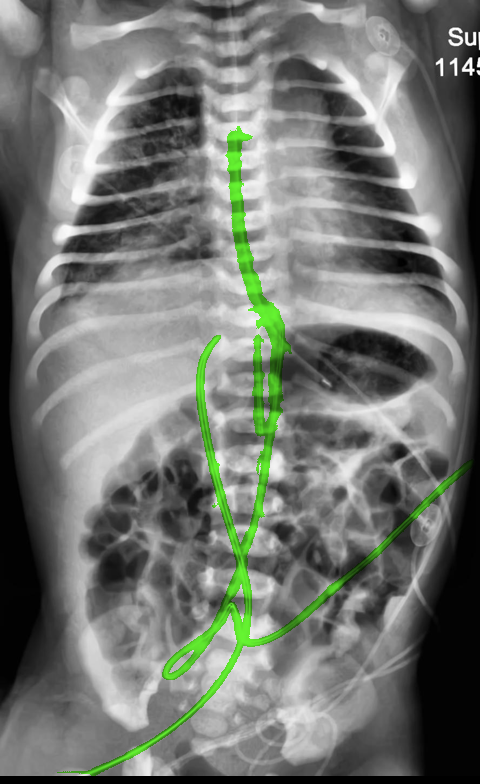

Automated catheter detection is a challenging task. Although most catheters have a radiopaque strip to facilitate detection, the strip may become less apparent depending on the projection angle. Catheters maybe confused by other similar linear structures like ECG leads and anatomy including ribs. Additionally, portions of catheters can be occluded by anatomical structures given that radiographs are a 2D projection of a 3D structure. For example, when a NGT is placed within the oesophagus, the catheter itself becomes less apparent due to the high density of the adjacent vertebrae. Finally, the number and type of catheters that could possibly appear in pediatric X-rays are unknown a priori. The catheters may be intertwined with each other thus making simple line tracing methods fail. Figure 1 gives three sample pediatric X-ray images with some common catheters highlighted in different colors.

To alleviate this annotation problem in catheter detection, we proposed to use X-ray images with simulated catheters by exploiting the fact that catheters are essentially tubular objects with various cross sectional profiles. To be more specific, a synthetic 2D projection of a catheter is generated by first simulating a horizontal catheter profile and then using it as a brush tip to draw along a B-spline path. This generated catheter is then composited with an X-ray image serving as the training data. Another contribution of this work is a segmentation network that can inherently take into account multi-scale information. This network adopts a UNet-style form and contains a recurrent module that can process inputs with increasing scales111Our code is available at https://github.com/xinario/catheter_detection.git.. We have empirically shown that by iterating through the scale space of the input image, higher recall is achieved as compared to using a single scale. Details about the methods are discussed in Section 3. Three sample detection results are shown in Figure 1.

The test dataset is collected locally and only contains frontal chest-abdominal X-rays from patients < 4 weeks old. This is the most common radiograph obtained to confirm placement of catheters such as UACs and UVCs in neonates. Currently, the test set has 35 fully labeled images with different catheter types with sample images previously shown in Figure 1. All the annotated catheters (lines excluding ECG leads) are treated as the same class in the detection.